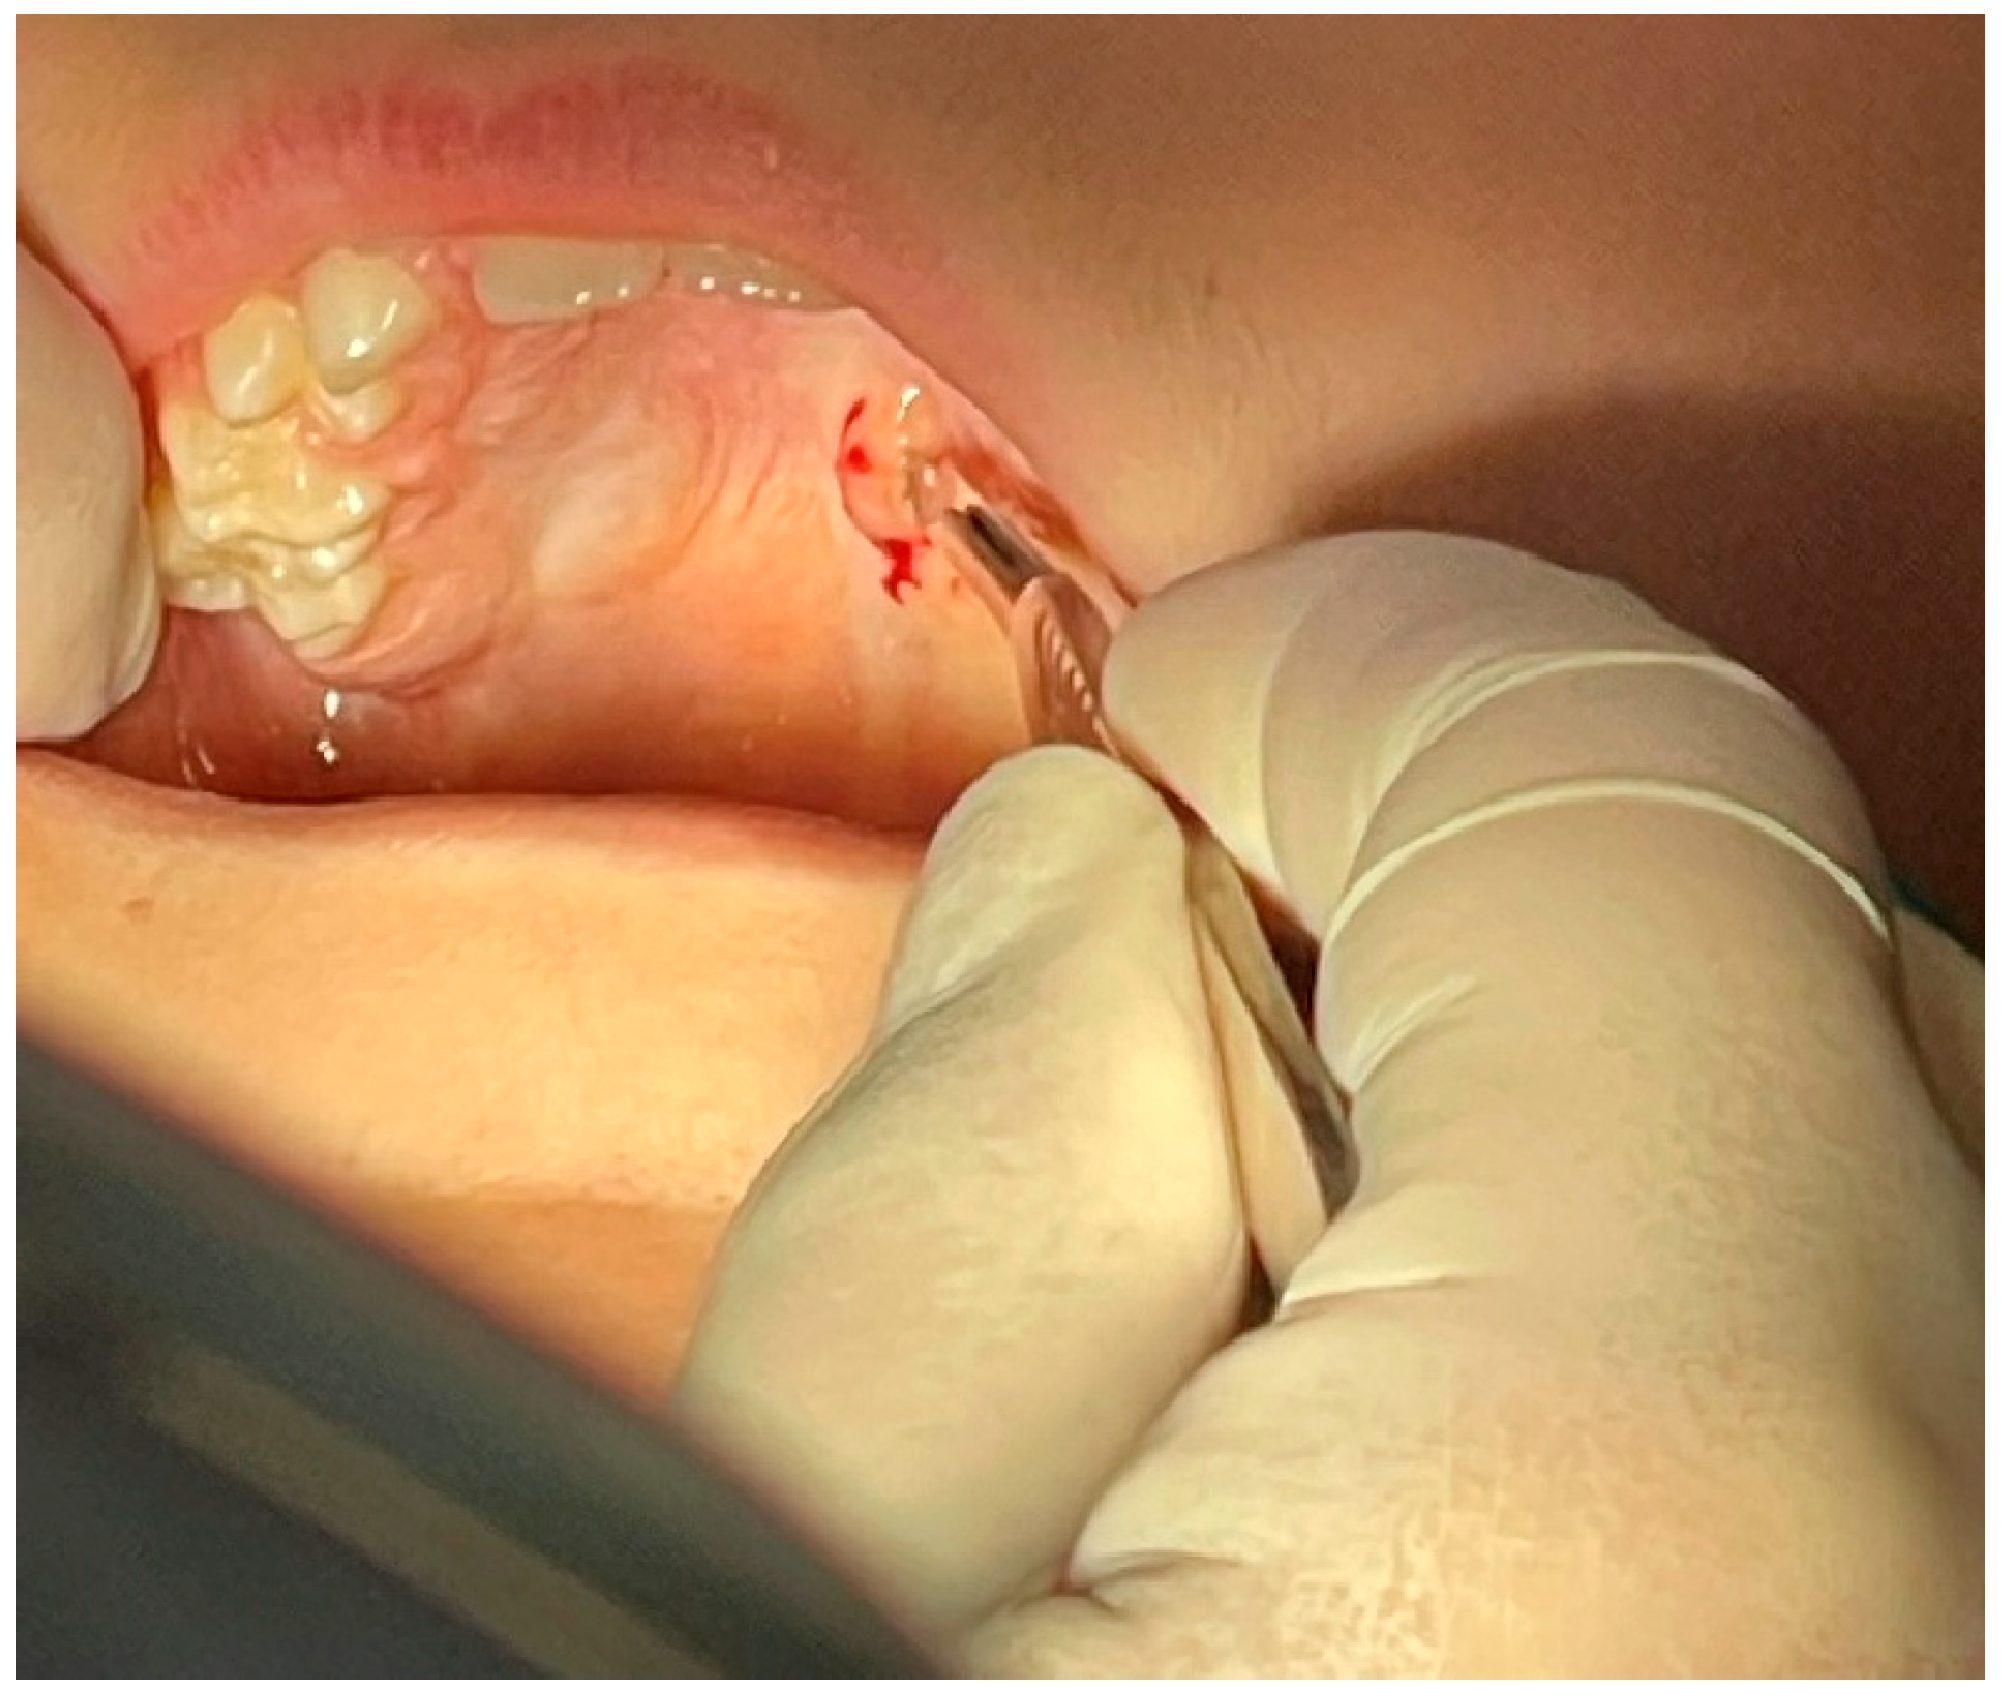

2. Case Presentation